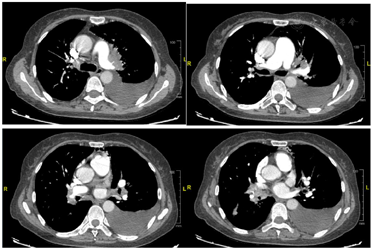

患者入院后完善血气分析、血常规、肝肾功能、电解质、凝血功能、B型钠尿肽未见明显异常。超声引导下行左侧胸腔穿刺置管引流术,胸水常规回报:淡黄色微浑胸水,比重1.010,黏蛋白定性实验1+,红细胞计数1000,有核细胞计数145,多核细胞19%,单个核细胞81%;胸水生化回报:总蛋白11 g/L,乳酸脱氢酶74.0 U/L,腺苷脱氨酶4.1 U/L,葡萄糖5.6 mmol/L,氯117 mmol/L,乳酸0.78 mmol/L。完善超声心动图提示:右心增大,二尖瓣反流(轻度),三尖瓣反流(轻-中度),左室舒张功能改变,射血分数正常,肺动脉高压(收缩压约84 mmHg)(三尖瓣反流估测)。下肢静脉超声未见血栓形成。完善气管镜检查:全麻下硬镜置入,气管环清楚,隆突锐利。左主支气管开口通畅,上下叶间嵴增宽,黏膜充血水肿;上叶黏膜充血水肿,可见碳末沉着,各叶段支气管开口闭塞;下叶黏膜充血水肿,可见碳末沉着,各叶段支气管开口狭窄。右主支气管开口通畅,上下叶间嵴增宽,黏膜充血水肿;上叶黏膜充血水肿,可见碳末沉着,各叶段支气管开口狭窄;中间干、中叶及下叶黏膜充血水肿,可见碳末沉着,中叶开口闭塞,下叶各叶段支气管开口狭窄。肺泡灌洗液细菌及真菌培养未见明显异常。肺泡灌洗液及淋巴结穿刺液X-PERT均为阴性。肺泡灌洗液流式:CD4/CD8 0.41%,巨噬细胞、鳞状细胞70.5%,淋巴细胞13.71%,中性粒细胞15.4%,嗜酸粒细胞0.39%。肺泡灌洗液NGS:细菌:表皮葡萄球菌、血链球菌;真菌:篮状菌属、绳状篮状菌、曲霉菌、杂色曲霉。病理:(左上肺门淋巴结穿刺细胞保存液)材料为多量红细胞及个别炎细胞。完善肺动脉增强CT(图1):两肺门增大,其内肺动脉不规则受侵,以左肺上叶、右肺中下叶受侵为著,右肺中叶支气管闭塞,右肺中叶不张,左肺上叶支气管受压变窄,以远左肺上叶肺组织可见大片实变影、树芽影及索条影;肺静脉受压变窄;两肺门及纵隔内多发肿大淋巴结;左侧胸腔引流管,左侧胸腔积液,右侧叶间积液。